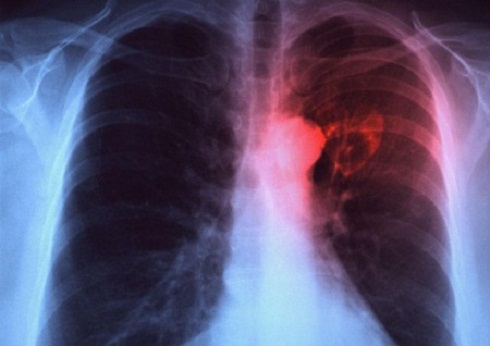

Sono 50 i comuni dell’area centrale salentina dove l’Istituto superiore di sanità (Iss) ha individuato un eccesso di tumori del polmone nei maschi, 3.846 decessi registrati, contro i 3.447 attesi. Il tasso di incidenza più elevato a Sogliano Cavour. Ma non va meglio a Soleto, Zollino e Castrì. In quest’area della provincia di Lecce la mortalità ha presentato un conto salato. Sono ben 67 i comuni che presentano un rischio superiore alla media nazionale. Fa eccezione il comune di Guagnano. Per le femmine tutti i comuni sono nella media, eccetto Lecce dove i decessi sono stati 248 rispetto ai 150 attesi.

Il tavolo interistituzionale tra Asl Lecce, Arpa, Provincia e Comune di Lecce, Inail,  Regione Puglia e gli enti di ricerca come l'Universita del Salento ed il Cnr ha evidenziato un’elevata incidenza di tumori polmonari nel sesso maschile. Dati poi confermati anche per il periodo 2006-2009 dall'Osservatorio Epidemiologico Regionale (Oer) e dal rapporto di mortalita ISTISAN per l’ anno 2012. Nel 2014 a Taranto l’Iss, evidenziava dei «cluster» di mortalita e incidenza per tumore polmonare in aree ben definite del Salento.

La «bestia nera» del tumore polmonare ha disegnato una poco invidiabile classifica che pone al vertice il distretto di Galatina, seguito da quelli di Poggiardo, Casarano e Maglie.

Uno studio dell’Iss dell’incidenza di tumori polmonari nei maschi ha evidenziato un cluster ben definito che include 16 Comuni dell’area centrale salentina (355 casi confermati contro 285 attesi) comprendenti i Comuni di Galatina, Galatone, Secli, Neviano, Aradeo, Collepasso, Cutrofiano, Sogliano, Soleto, Sternatia, Zollino, Maglie, Melpignano, Castrignano dei Greci, Corigliano.